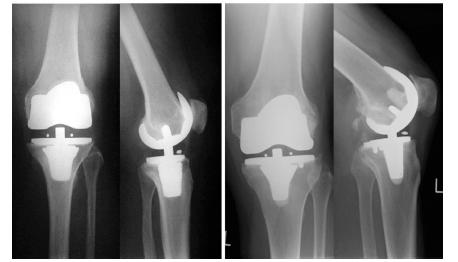

Twenty-four patients (25 TKRs) underwent a preoperative clinical evaluation and then a postoperative evaluation after 26.2 months in the allergy group treated with coated implants (n=13 implants) and after 24.5 months in the control group treated with uncoated implants but identical geometry (n=12) using HSS, WOMAC and SF-36 scores. Radiological evaluations were performed using standard anterior-posterior (a.p.) and lateral X-rays.

During follow-up two patients of the allergy group had to undergo revision surgery due to non-implant-related reasons. A comparative analysis of both study groups showed a significant difference in the HSS scores at both evaluation time points (MW test p≤0.050); these findings are remarkable since the control group had a significantly lower score preoperatively (54.0 vs 65.0 points) and a significantly higher score (82.5 vs 75.0 points) postoperatively. The preoperative and postoperative WOMAC and SF-36 scores were comparable in both groups (MW test p≥0.052), although the postoperative increase in the score for the allergy group was lower. The radiological results were comparable in both groups and were unlikely to influence the results.

24例患者(25次TKR)在术前进行了临床评估,然后在使用HSS、WOMAC和SF - 36评分的情况下,对接受涂层植入物治疗的过敏组(n = 13个植入物)术后26.2个月以及接受未涂层但几何形状相同的植入物治疗的对照组(n = 12)术后24.5个月进行了评估。使用标准前后位(a.p.)和侧位X线进行放射学评估。

在随访期间,过敏组有2例患者因非植入物相关原因接受了翻修手术。两个研究组的比较分析显示,在两个评估时间点的HSS评分均有显著差异(MW检验p≤0.050);这些发现很显著,因为对照组术前评分显著较低(54.0对65.0分),术后评分显著较高(82.5对75.0分)。两组术前和术后的WOMAC和SF - 36评分相当(MW检验p≥0.052),尽管过敏组术后评分的增加较低。两组的放射学结果相当,不太可能影响结果。